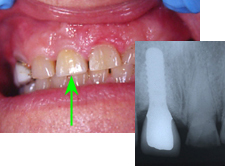

Ein 32 Jahre alter Mann kommt im November 1984 mit Zahnweh am unteren linken, zweithintersten Molaren (Backenzahn) in die Praxis. Das Röntgenbild von Abb. 1 zeigt insuffiziente Wurzelfüllungen bei allen drei Wurzelkanälen und an den Wurzelspitzen sogenannte Granulome, sichtbar als schwarze Flecken (grüne Pfeile in Abb. 1).

In Abb. 2 ist das Röntgenbild 22 Jahre nach korrekter Wurzelbehandlung mit dem nun überkronten Zahn zu sehen. Der Knochen um die Wurzelspitzen ist entzündungsfrei gesund.